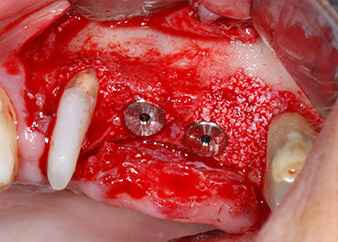

Dann wurden die Implantate (Restore, Keystone Dental) mit dem Implantatmotor eingesetzt (Abb. 11 und 12).

Knochendefizite an der mesialen Fläche des Zahns 27 und an der bukkalen Wurzel des Zahns 24 wurden mit xenogenem Knochenersatzmaterial aufgefüllt und mit einer resorbierbaren Kollagenmembran (Geistlich Bio-Gide) im Sinne einer GBR-Augmentation (Abb. 13 und 14) abgedeckt.